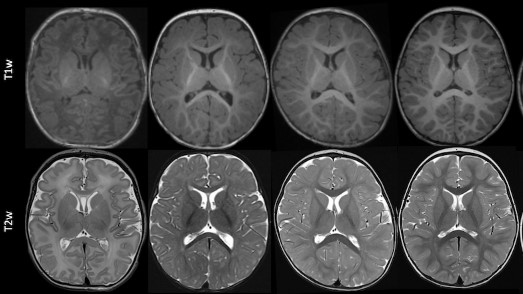

#RSNA22 is in the books, it was such a great meeting with so many wonderful people. I am especially grateful to the @RSNA for being awarded a Trainee Research Prize for our work on atrial flow and silent brain infarctions @NURadiology #4DFlow